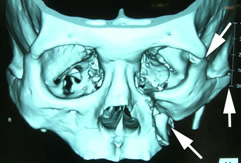

![]() |

また、骨折の状態によって、眼窩骨骨折と同様に3Dモデルを作成するシミュレーションサージャリーを行っています。 |

| 頬骨骨折3次元CT像 |